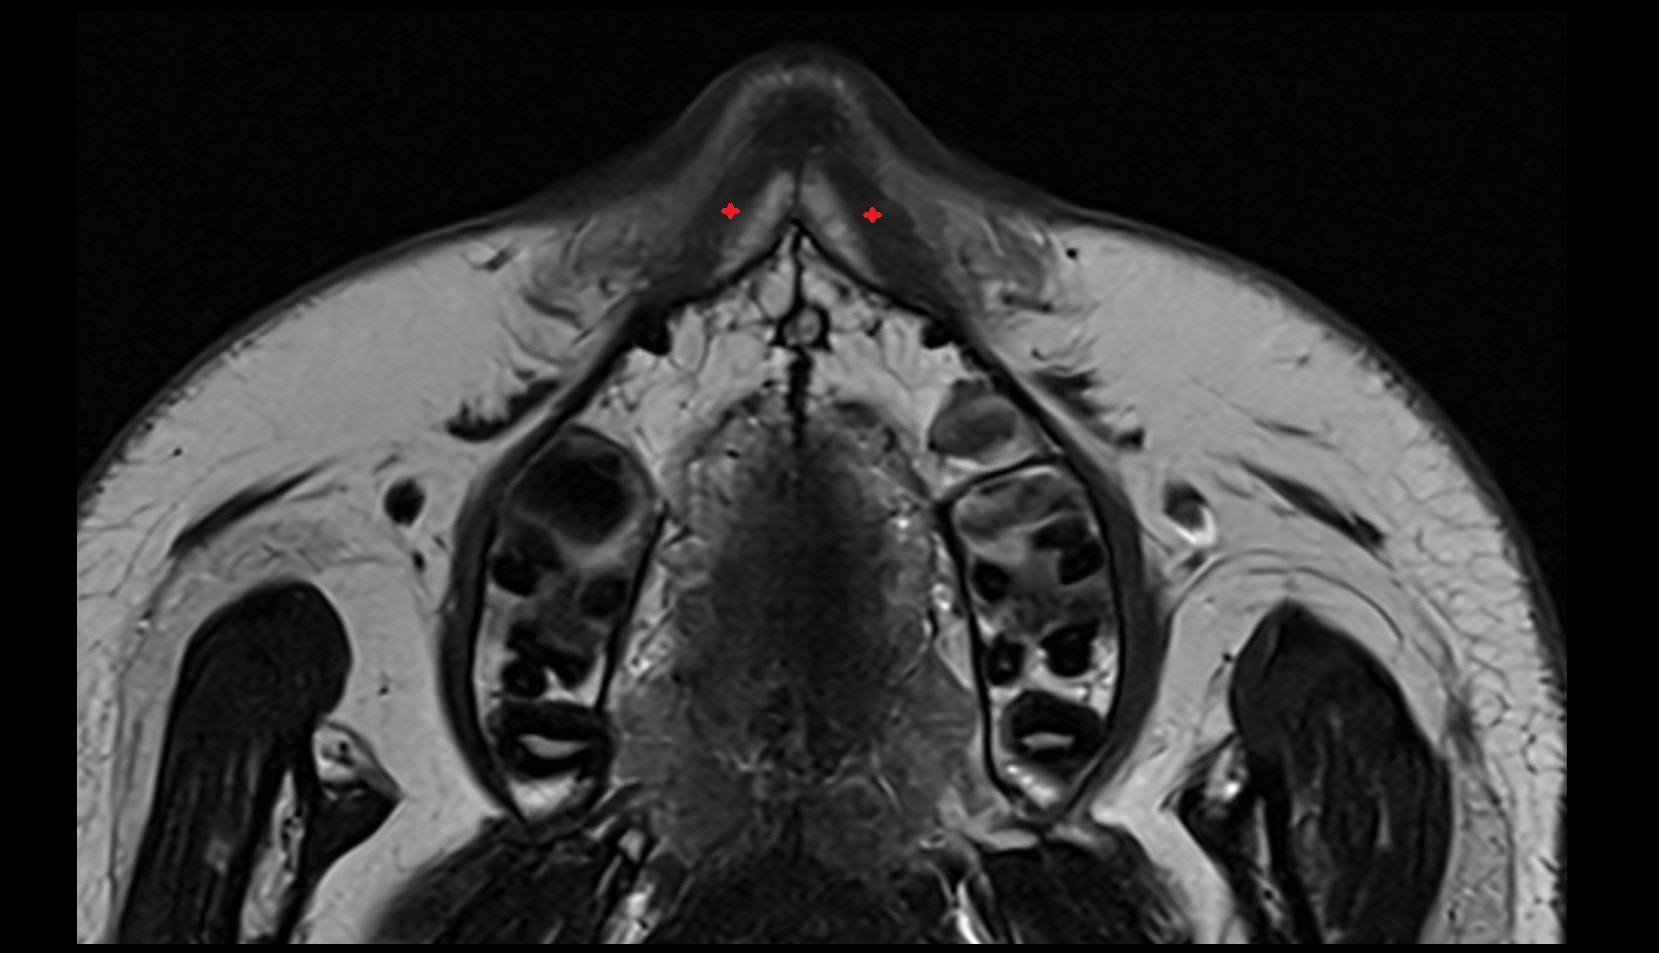

- Hippocampal head

- Head of hippocampus